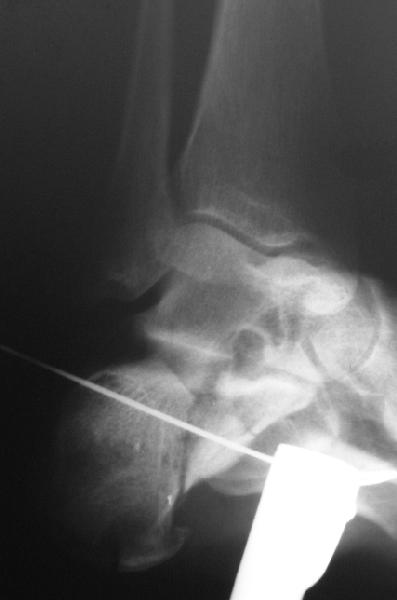

Кроме стандартных снимков, необходим контроль конгруэнтности суставной поверхности (проекции Бродена)